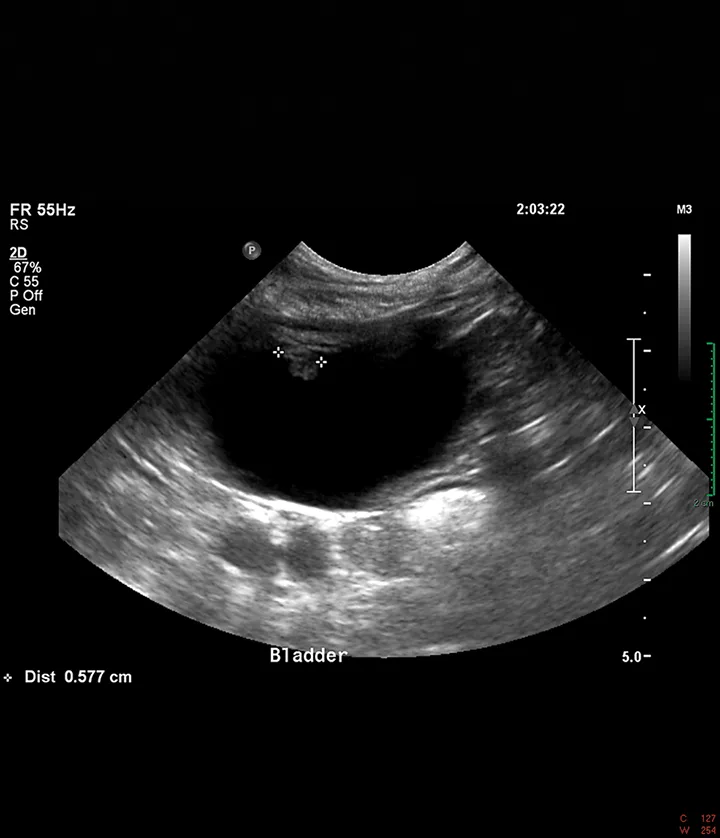

Abdominal ultrasound showed a mildly thickened cranioventral urinary bladder wall with a 6-mm irregular, polypoid, inhomogeneous mass extending into the lumen (Figure 1). No other abnormalities were identified in the abdomen. Cystoscopy revealed an irregular mass on the cranioventral wall with an area of ulceration and a fibrous tag protruding into the lumen (Figure 2). The remainder of the bladder appeared friable. Aerobic and Mycoplasma spp cultures of the bladder wall were negative. Histopathologic examination of biopsies showed mild lymphocytic cystitis.

FIGURE 1

Ultrasound image of a 6-mm polypoid mass extending into the lumen from the cranioventral bladder wall